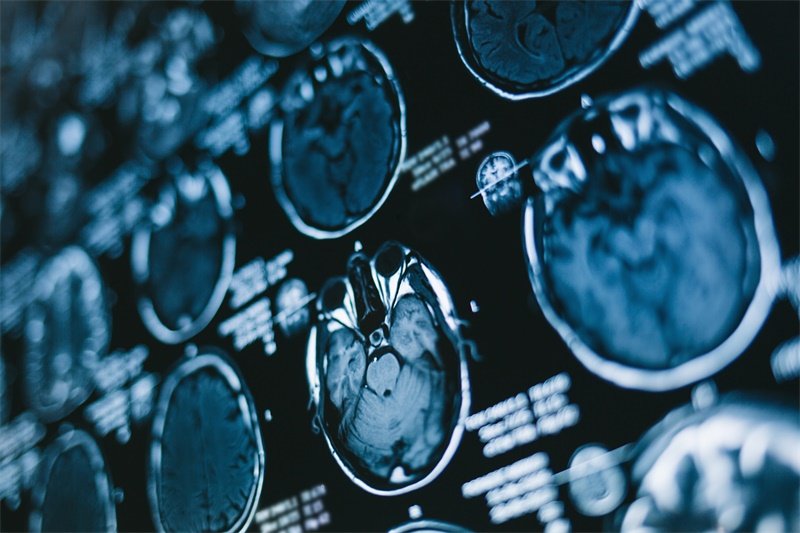

影像学检查

影像学检查是诊断的关键,常用的有CT扫描和MRI。CT扫描能够清晰显示骨结构的细微变化,帮助识别肿瘤及其大小。MRI则更加精细,能清晰展现软组织的情况,尤其对于评估围绕神经及血管的病变效果非常明显。